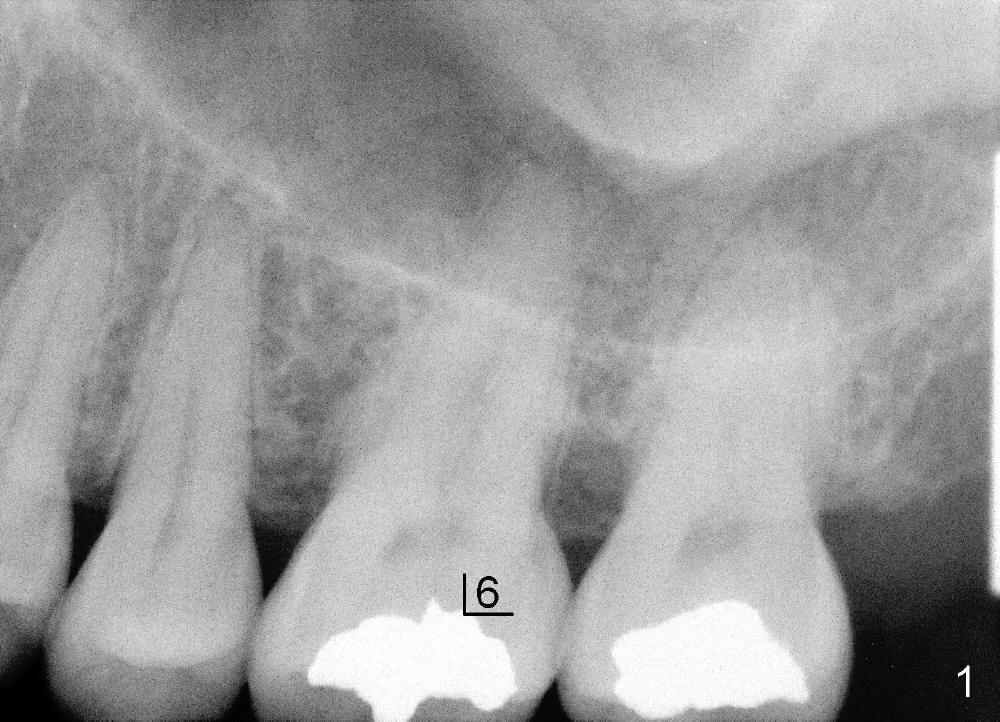

A 49-year-old lady has toothache at the upper left 1st molar (Fig.1).  Removal of the occlusal amalgam reveals crack lines (Fig.2).  After atraumatic extraction (sectioning), osteotomes are used to form osteotomy in the septum (Fig.3 S).  Finally the osteotomy seems to drop into the palatal socket.  No bone graft is used.  The socket is closed by elavating the buccal flap (Fig.3) and severing the periosteum.  Periodontal dressing is applied for wound protection (Fig.4 P). Is the implant in the sinus (S)?